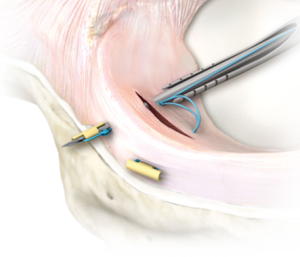

آرتروسکوپی

در برخی موارد، پزشک ممکن است از ابزاری به نام آرتروسکوپ برای بررسی داخل زانو استفاده کند.(تصویر شماره ۲) آرتروسکوپ از طریق یک برش کوچک در نزدیکی زانوی شما وارد می شود. این دستگاه حاوی یک نور و یک دوربین کوچک است که تصویر بزرگ شده ای از داخل زانوی شما را روی مانیتور ارسال می کند. در صورت لزوم، ابزارهای جراحی را میتوان از طریق آرتروسکوپ یا از طریق برشهای کوچک اضافی در زانوی شما برای اصلاح یا ترمیم پارگی وارد کرد.

تصویر شماره ۲ : آرتروسکوپی